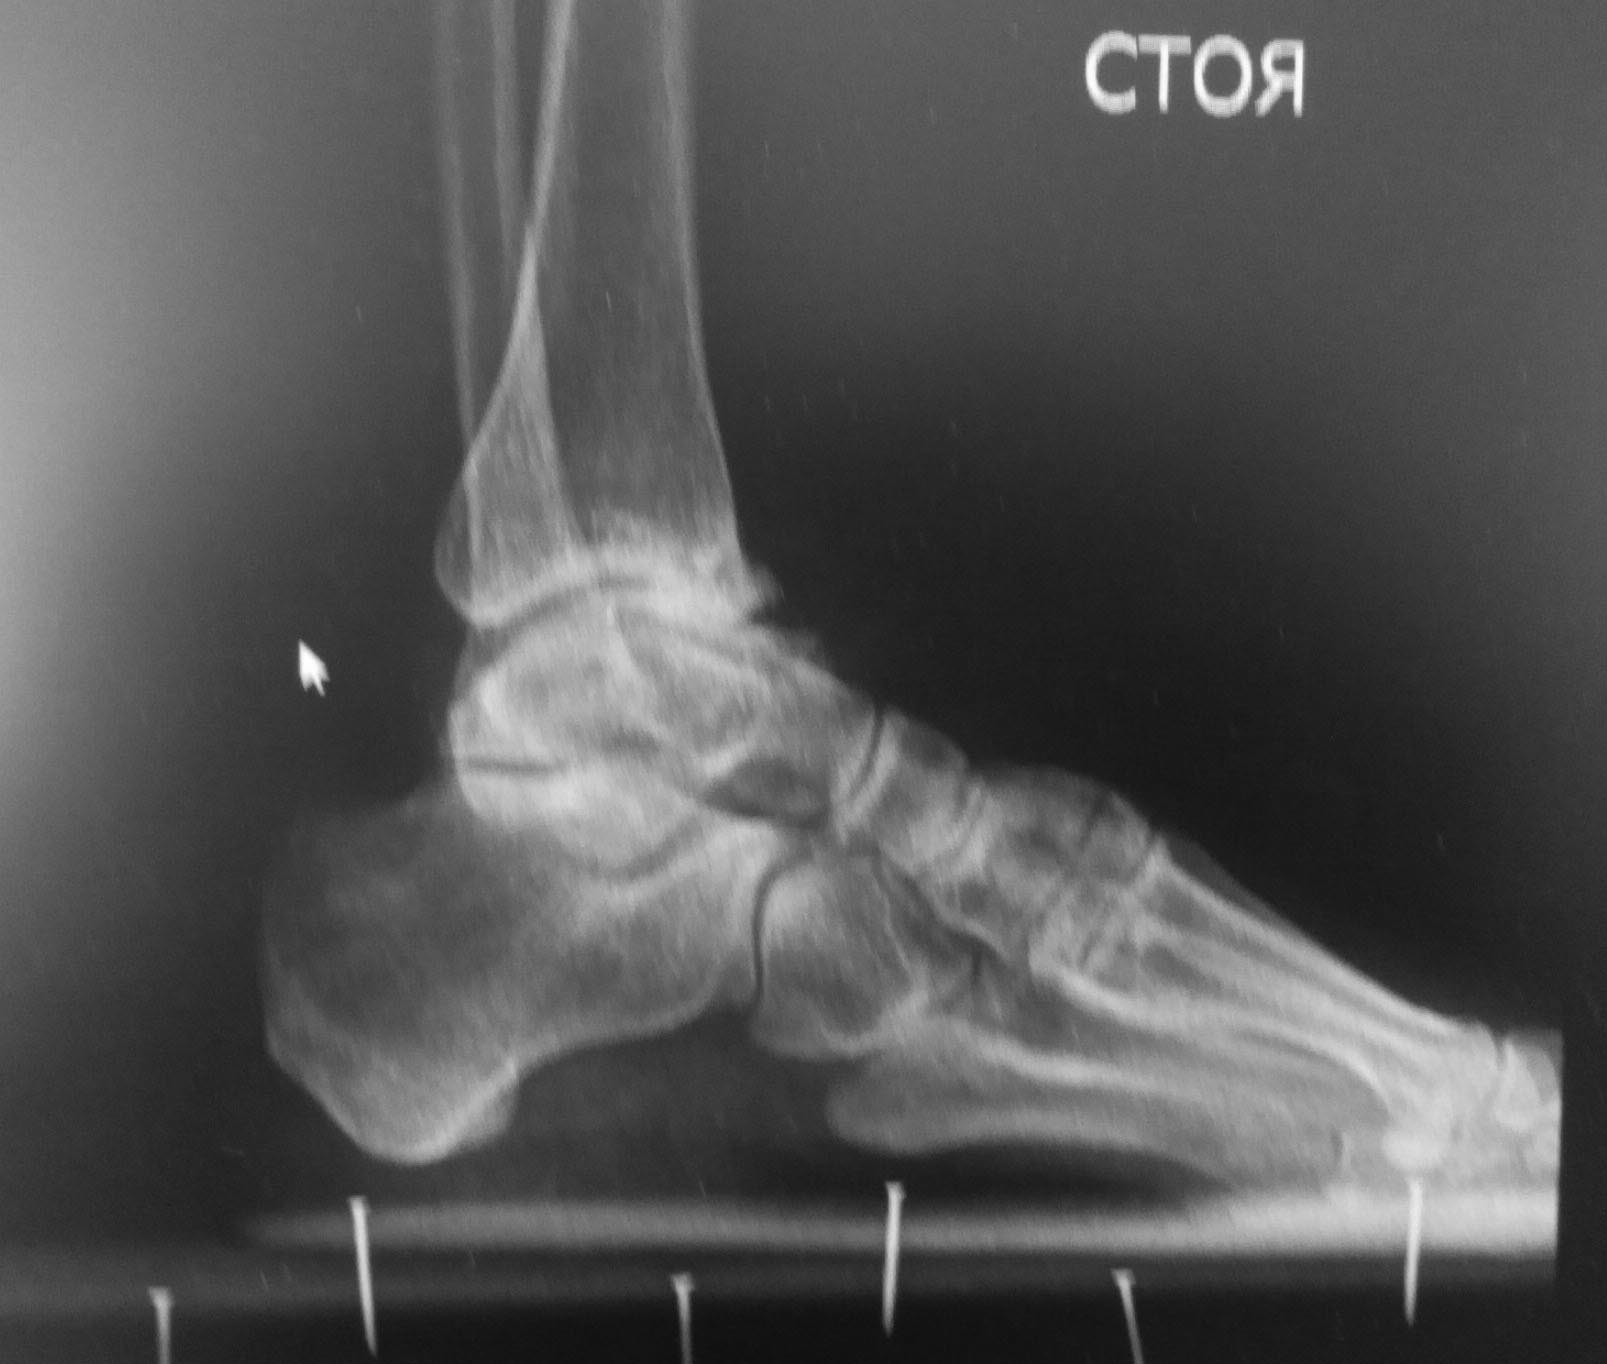

Деформация голеностопного сустава

Добрый день! Обратилась женщина 1975 г.р с болями в правом голеностопном суставе.

Случай обсуждался здесь. Только сейчас появилась возможность сделать Rg с нагрузкой. За это время (с апреля 2016 г.) усилились боли и деформация.Какова тактика лечения на ваш взгляд в данном случае?

Уважаемые, а не была ли тут травма в/3 малоберцовки (я имею в виду надсиндесмозную травму голеностопного сустава) с разрывом синдесмоза. Возможно такой вариант: пробовать востановить целостность синдесмоза (может быть даже с остеотомией для востановления длинны м/берцовой кости) c жесткой фиксацией, и втом случае если устранится подвывих и будет стабилен сустав на этом и успокоится. Благодарю за внимание.

Неестественная форма таранной кости позволяет предположить, чт травма была на фоне уже существующей патологии. Хотелось бы получить ответ на ряд вопросов: 1. Не было ли проблем со стопой с раннего детства? 2. Не было ли пареза малоберцового нерва, "шлепающей" стопы"? 3. Нет ли гипотрофии икроножной мышцы? 4. Нет ли внешних признаков стопы Фридрейха?В любом случае наверное предпочтителен артродез, но хотелось бы точнее определиться с диагнозом, кроме артроза.

Конечно нужно смотреть клинически, но по рентгенограмме можно предположить передний импиджмент. Возможно ремоделирование переднего края большеберцовой облегчит страдания пациентки.